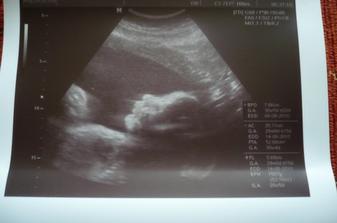

Jinak těch kontrol asi máme málo v březnu(6),tak jsme si 10.3. jeli pro změnu zase do Brna.Odpoeldne jsme trochu zašpinila a bolel mě podbřišek.Dr nás vyšetřila a vše je v pořádku.Akorát nad čípkem je malá trhlinka,od tud asi to špinění(asi od zavádění čípků).Jinak je vše jak má být,děloha,čípek,miminko.Vážíme 215gr,byli jsme včera 19+0,ale odpovídáme 18+0,ale nám to nevadí,určitě to doženem.Paní dr o mě prohlásila,že jsu živel,ukázala ammince srdíčko,oči a močový měchýř.A to nejduležitější-není to se 100%jistotou,ale vypadáme na HOLČIČKU.Akorát u toho nebyl manžílek,ale to prý nevadí,hlavně,že jsme obě v pořádku.

Ale na uz jsme viděli vše co máme mít,jsme zdravýakorát o týden mín,ale to už od začátku.Navíc jsme viděli něco s čím jsme nepočítali-pindíka.Takže Nelinka nebude,ale to nám nevadí,hlavně aby jsme byli oba v pořádku-my i náš malý CHLAPEČEK.